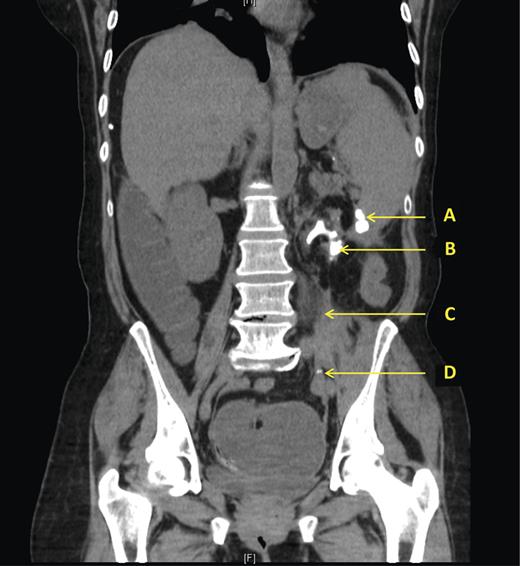

A subsequent CT scan confirmed the presence of xanthogranulomatous pyelonephritis and established that the second area of calcification was a 1.5 × 1.0 × 2.5 cm perforated extra-renal fragment of calculus positioned adjacent to the proximal descending colon.

This stimulated a diffuse inflammatory response in the left upper quadrant, resulting in a prominent thick-walled proximal descending colon with an abrupt calibre change in the mid descending colon, mesenteric fat stranding, a thickened ileo-psoas muscle with fragments of calculi in the left iliac fossa, gross lymphadenopathy and inflammatory changes around the spleen. (Fig. 2)

CT scan showing (A) Extra-renal fragment of calculus adjacent to transition point in thickened descending colon. (B) Staghorn calculus within atrophic left kidney with surrounding inflammation. (C) Thickened inflamed psoas muscle. (D) Fragments of calculus in LIF.